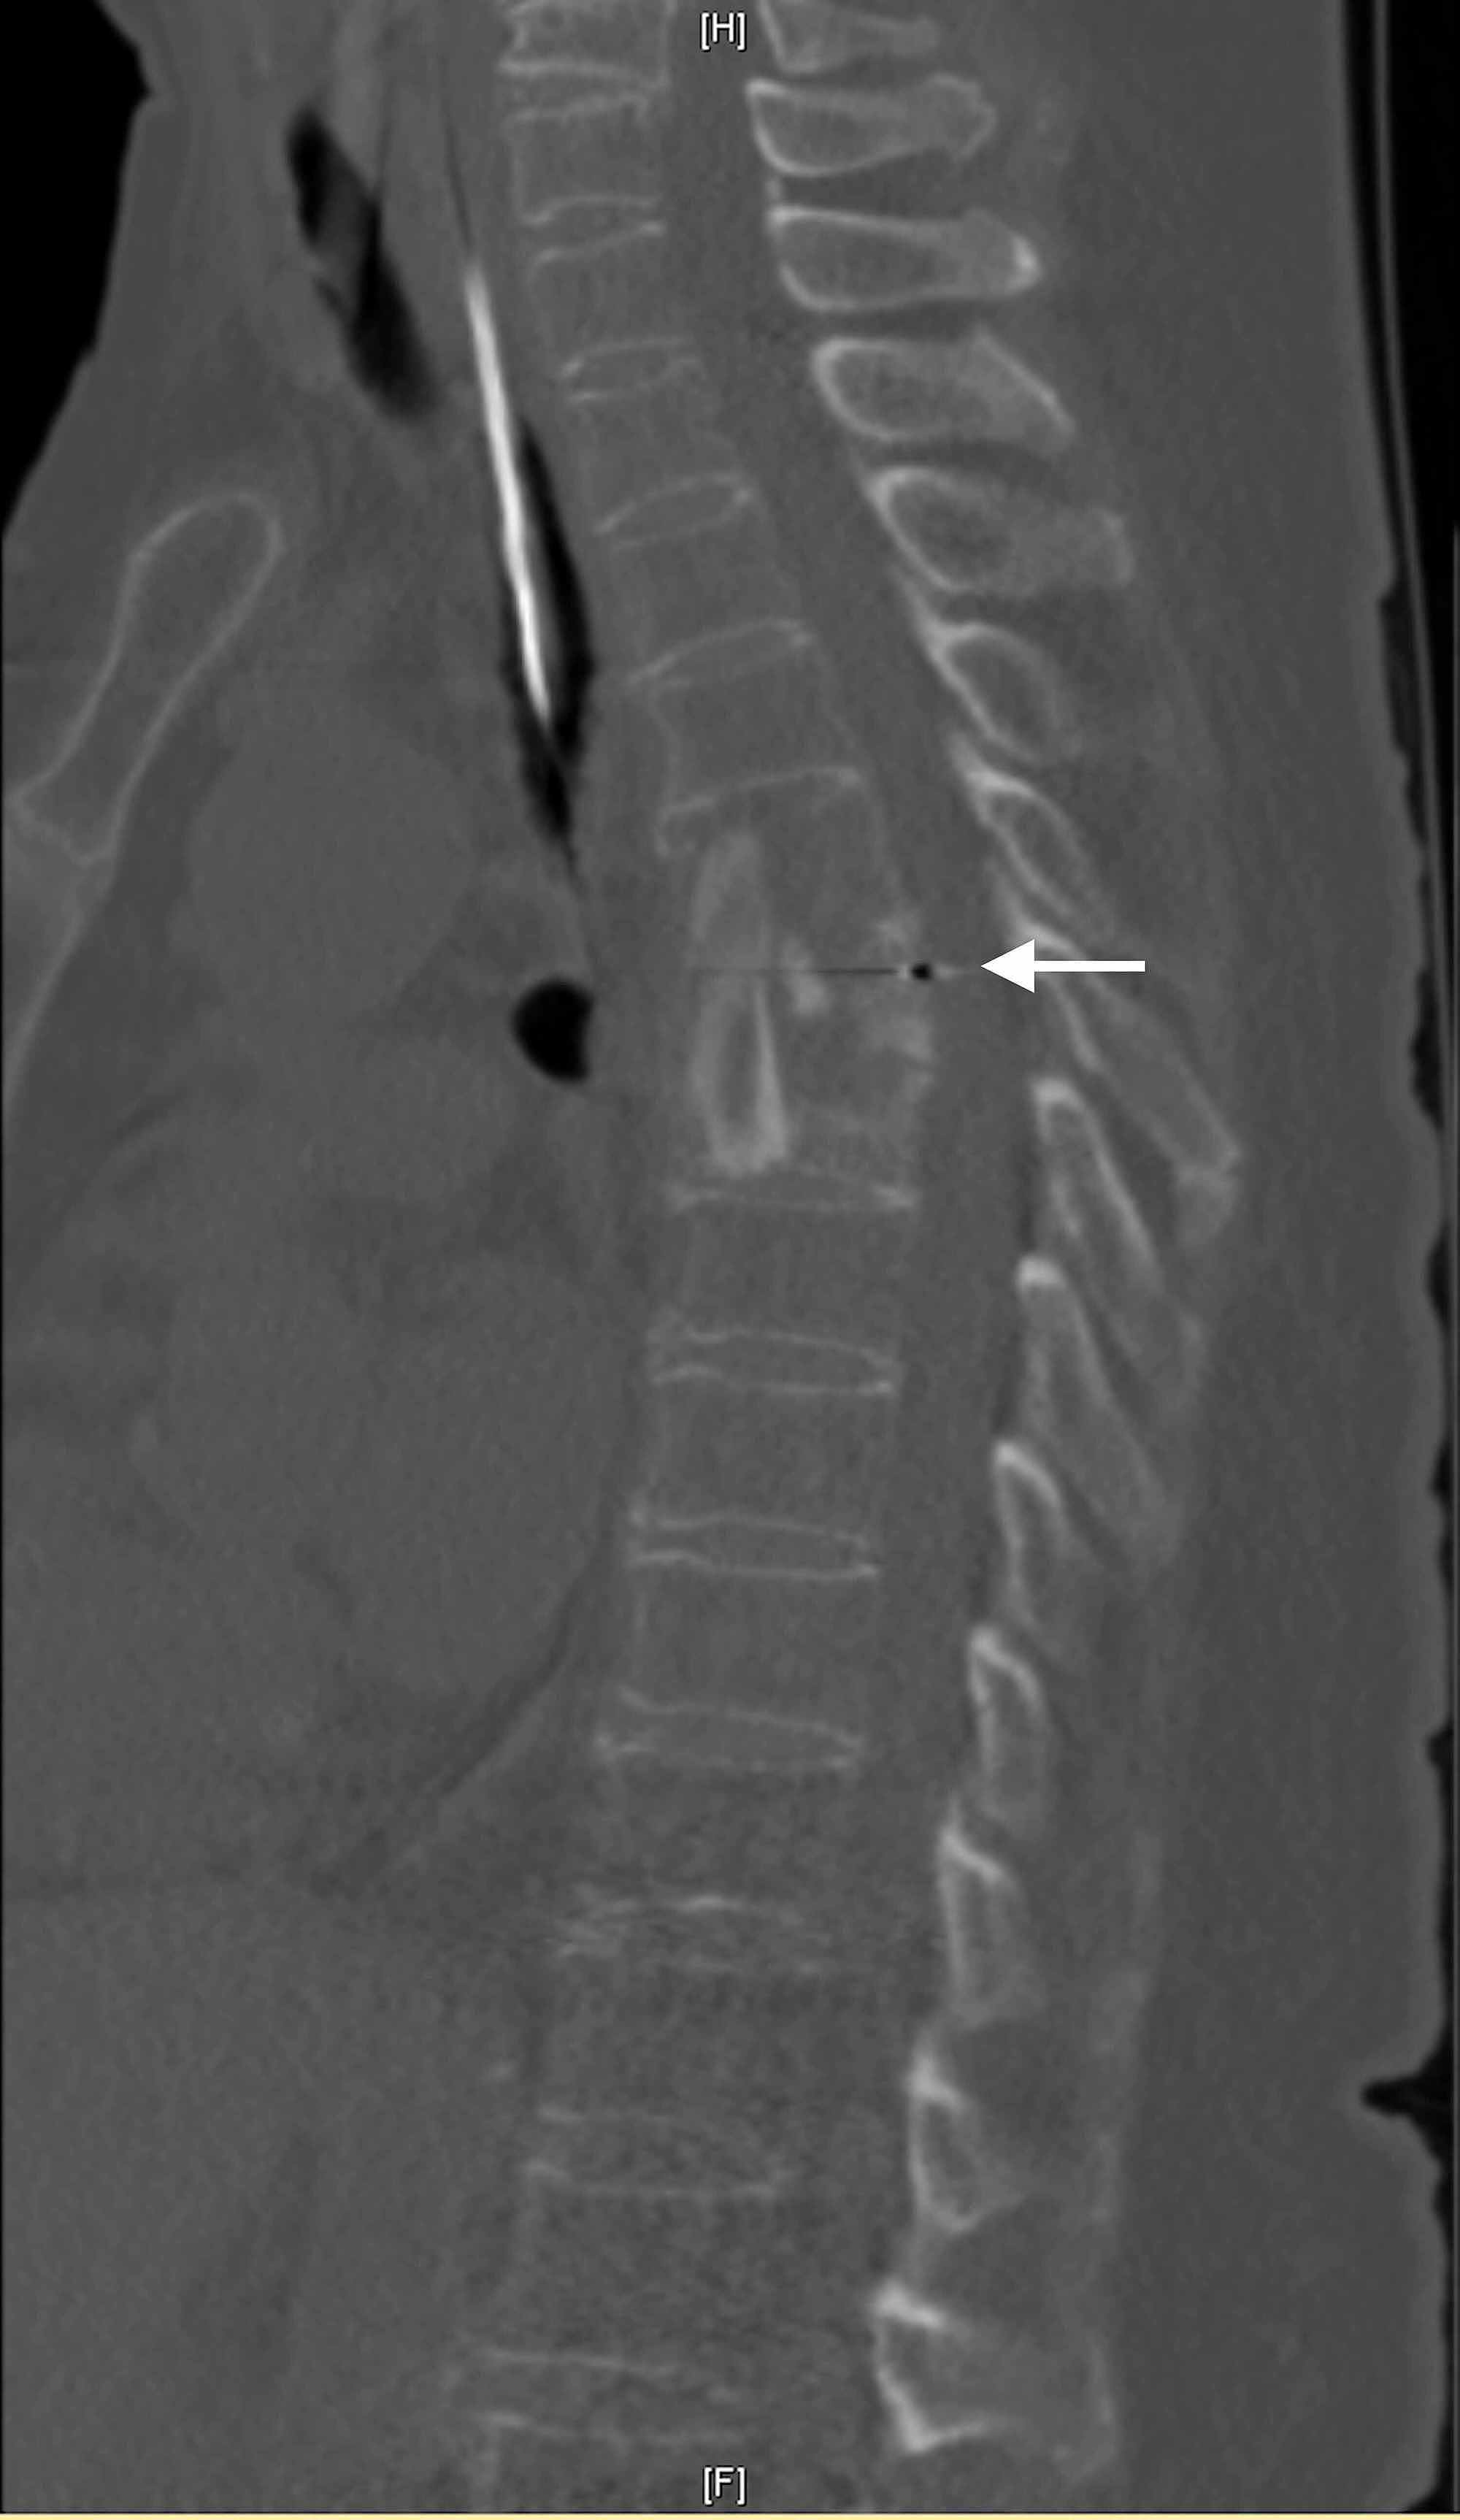

Showing contiguous and skip lesions in Pott’s spine. a Spinal MRI of a

Showing contiguous and skip lesions in Pott’s spine. a Spinal MRI of a Pott's Disease Contagious It originates in a vertebral body and spreads to. Describe the testing that should be done if pott disease is suspected. Identify the signs and symptoms that should lead a practitioner to consider pott disease. Once it passes from an infected person to another, it can spread from the lungs to other body parts, including the spine. tuberculosis is a. Pott's Disease Contagious.